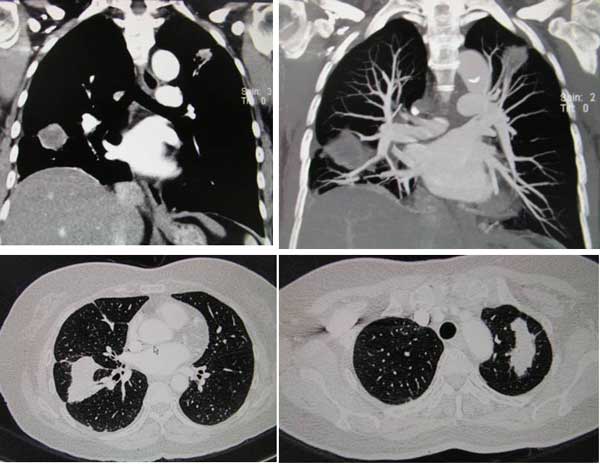

His cancer responded to the treatment — My lungs, speckled with innumerable tumours before, were clear except for a one-centimetre nodule in the right upper lobe … there had been a clear, dramatic reduction in tumour burden.

Meaningless shrinkage of tumour by Iressa

These two cases happened with patients in Jakarta (above) and in Malaysia (below). And this also happened some years later with Dr. Paul in Stanford. What can we learn from such cases?